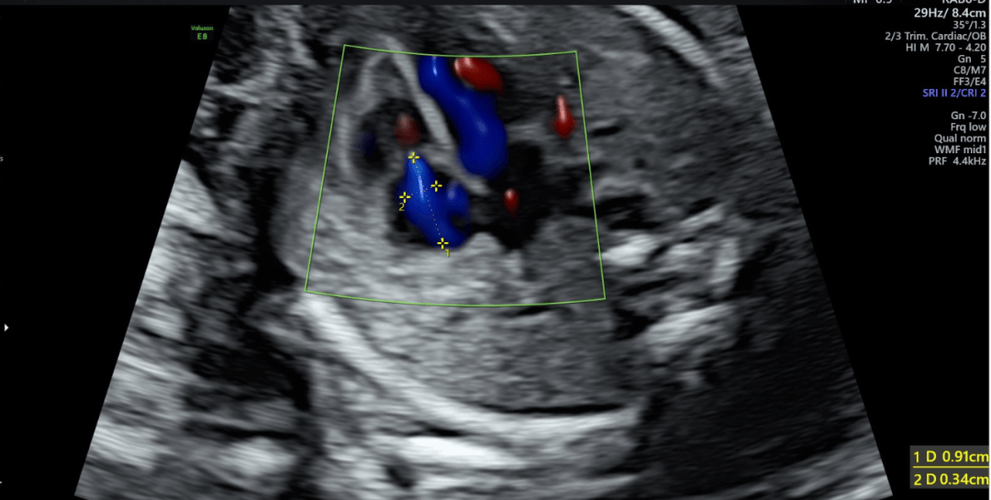

- 新生儿心脏超声(金标准):这是诊断和评估三尖瓣返流最重要、最准确的检查,它可以清晰地显示:

- 三尖瓣的结构、瓣叶数量、形态和位置是否正常。

- 返流的位置、范围和速度,从而量化返流的严重程度。

- 右心房、右心室的大小和功能。

- 肺动脉压力是否增高。

- 是否合并其他心脏畸形。